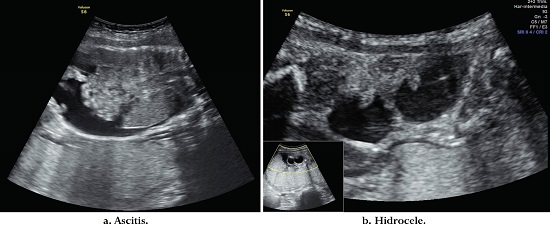

Examen físico: frecuencia cardiaca 100 lpm, presión arterial 120/ 70 mmHg. Altura uterina de 28 cm y fetocardia 144 lpm. Se toman paraclínicos. Hemograma: leucocitos 10 300 x mcl, neutrófilos 70% Hb:11 gr/dl, hematocrito 33, plaquetas: 326 000 x mcl, proteína C reactiva 20 mg / L, creatinina: 0,7 mg/ dl, hepatitis B: negativa, prueba VIH: negativa, prueba treponémica rápida: positiva. VDRL: 1024 diluciones. Se realizó diagnóstico de caso confirmado de sífilis gestacional. Ultrasonido obstétrico mostró: biometría para 26 semanas. Crecimiento fetal normal. Líquido amniótico normal. Hallazgos positivos: hídrops fetal con presencia de ascitis, derrame pericárdico e hidrocele bilateral; además, presencia de hepatomegalia (Figura 2). Se hospitalizó, se inició esquema de maduración pulmonar fetal, neuroprotección fetal con sulfato de magnesio y tratamiento con penicilina endovenosa de 5 millones de unidades cada 4 horas por 14 días por considerar sífilis gestacional con afectación fetal severa. Se dio tratamiento a la pareja con penicilina benzatínica 3 dosis. Evolución: el Doppler de arteria cerebral media sin evidencia de anemia fetal, en la hospitalización se realizó monitoria fetal por turno. Control con ecografía y doppler a los 7 días: doppler de anemia cerebral media normal. Líquido amniótico normal. Persistencia de ascitis y hepatomegalia. Control ecográfico a los 14 días: Doppler de anemia cerebral media normal. Líquido amniótico normal, persistencia hepatomegalia, sin ascitis. Se da salida y control ecográfico semanal.

En la semana 37 ingresó la paciente en trabajo de parto, fase latente, se realizó refuerzo con oxitocina; durante el trabajo de parto presentó cifras de presión arterial en rango de severidad que cedieron con nifedipino. Se inició sulfato de magnesio para profilaxis de eclampsia. Paraclínicos de perfil toxémico en límites normales. VDRL reportado: 1, 1024 diluciones. Valorada por el servicio de infectología quien formula penicilina benzatínica 2,400,000 UI IM, una dosis semanal por tres semanas; y a la pareja quien refiere no cumplió la indicación inicial de tratamiento. Se atendió parto vaginal obteniendo producto de sexo masculino de peso 2,325 g con adaptación neonatal adecuada. A las 72 horas del puerperio se dio salida de la madre sin complicaciones. Sin antihipertensivo. Al recién nacido se le toma VDRL a las 12 horas: 1:16 diluciones, se realizó estudio para sífilis congénita y recibió tratamiento con penicilina endovenosa por 14 días, posterior a lo cual se dio egreso sin complicaciones.